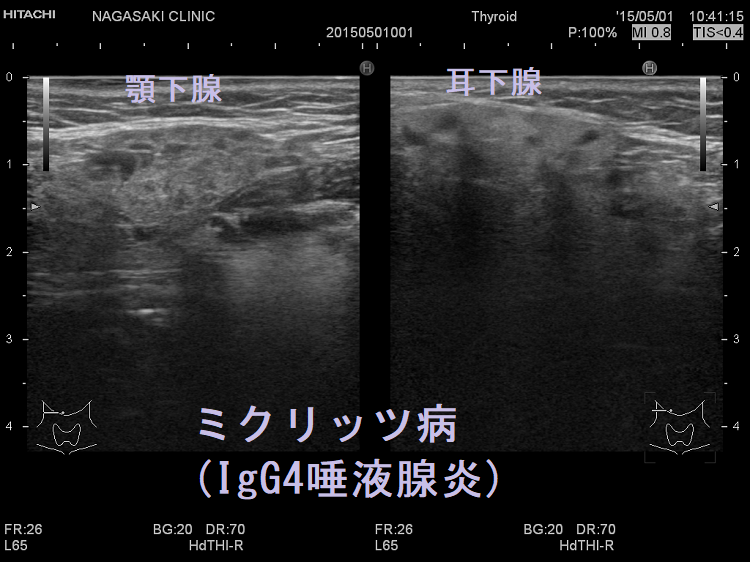

ミクリッツ病(Mikulicz病、IgG4唾液腺炎、IgG4関連硬化性唾液腺炎)はシェーグレン症候群と非常に類似しているが、シェーグレン症候群に特異的な抗SS-A抗体/抗SS-B抗体はほとんど陰性です。

ミクリッツ病にIgG4関連甲状腺炎を合併した報告があります。[Eye Sci. 2014 Mar;29(1):47-52.]

珍しい顎下腺のカットナー腫瘍(慢性硬化性唾液腺炎:Küttner tumour:kuttner tumor)は、ミクリッツ病(IgG4関連硬化性唾液腺炎)と同じIgG4関連疾患で、限局型IgG4関連硬化性唾液腺炎。